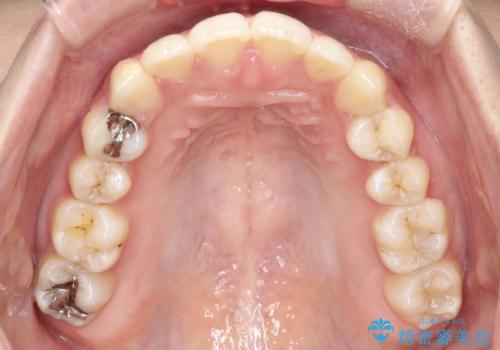

驚くほど短期間で前歯のガタツキを解消! マウスピース矯正の効果

奥歯の噛み合わせは綺麗に噛んでいたため、前歯の叢生(でこぼこ)を、短期間で治療完了するように計画しました。

奥歯の噛み合わせは整っていたため、前歯の並びを美しく修正することに専念できました。マウスピース矯正による治療で短期間で改善しました。

前歯のガタツキを改善する治療法として、マウスピース矯正が適していることが多いです。

マウスピース矯正は、金属製のブラケットやワイヤーを使用せずに、透明なマウスピースを装着して歯を移動させる方法です。そのため、目立たず、痛みも少ないです。